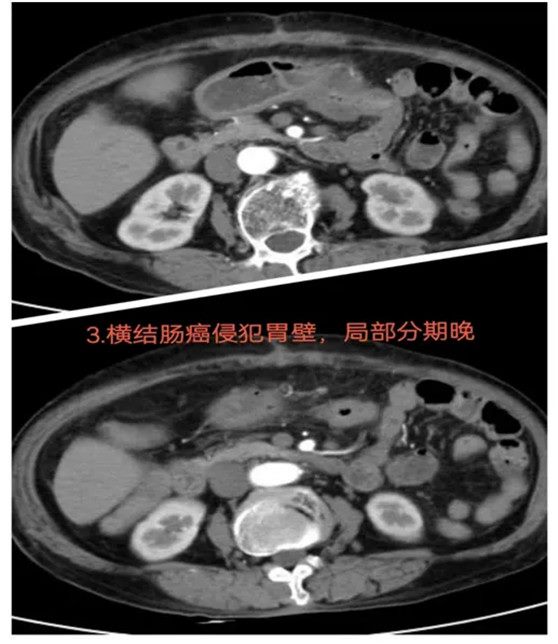

03结肠癌侵犯胃壁:迎难而上的手术抉择

患者4个月前因横结肠恶性肿瘤在外院接受手术治疗,但由于手术困难,原定手术被中止,仅行近端结肠造口术。随后,患者转入郑州大学五附院接受进一步治疗。经过多学科会诊及充分的术前准备,科室决定迎难而上,尝试再次进行手术切除。通过反复阅片和科内讨论,最终制定了详细的手术方案。术中探查发现,横结肠癌已侵犯胃壁,进一步增加了手术难度。最终,患者成功接受了经腹腔镜下横结肠癌根治术,并对受侵胃壁进行部分切除,同时进行了结肠造口还纳术。术后恢复良好。

难点总结:本病例的难点主要在于肿瘤侵犯了胃壁,导致手术范围和操作难度大大增加。虽然患者此前手术中止,但通过多学科评估和详细的术前准备,手术团队成功克服了这些挑战。

推荐理由:该病例展示了面对复杂肿瘤侵犯和手术难度增加的情况下,团队通过多学科协作和充分术前准备,成功完成了高难度手术。特别是在肿瘤侵犯胃壁的情况下,手术方案的精确制定和腹腔镜技术的应用确保了肿瘤的根治性切除,并有效进行了结肠造口还纳术。术后患者恢复顺利,腹部症状明显减轻,体现了精准治疗和细致术前评估的重要性,为类似病例提供了宝贵经验。